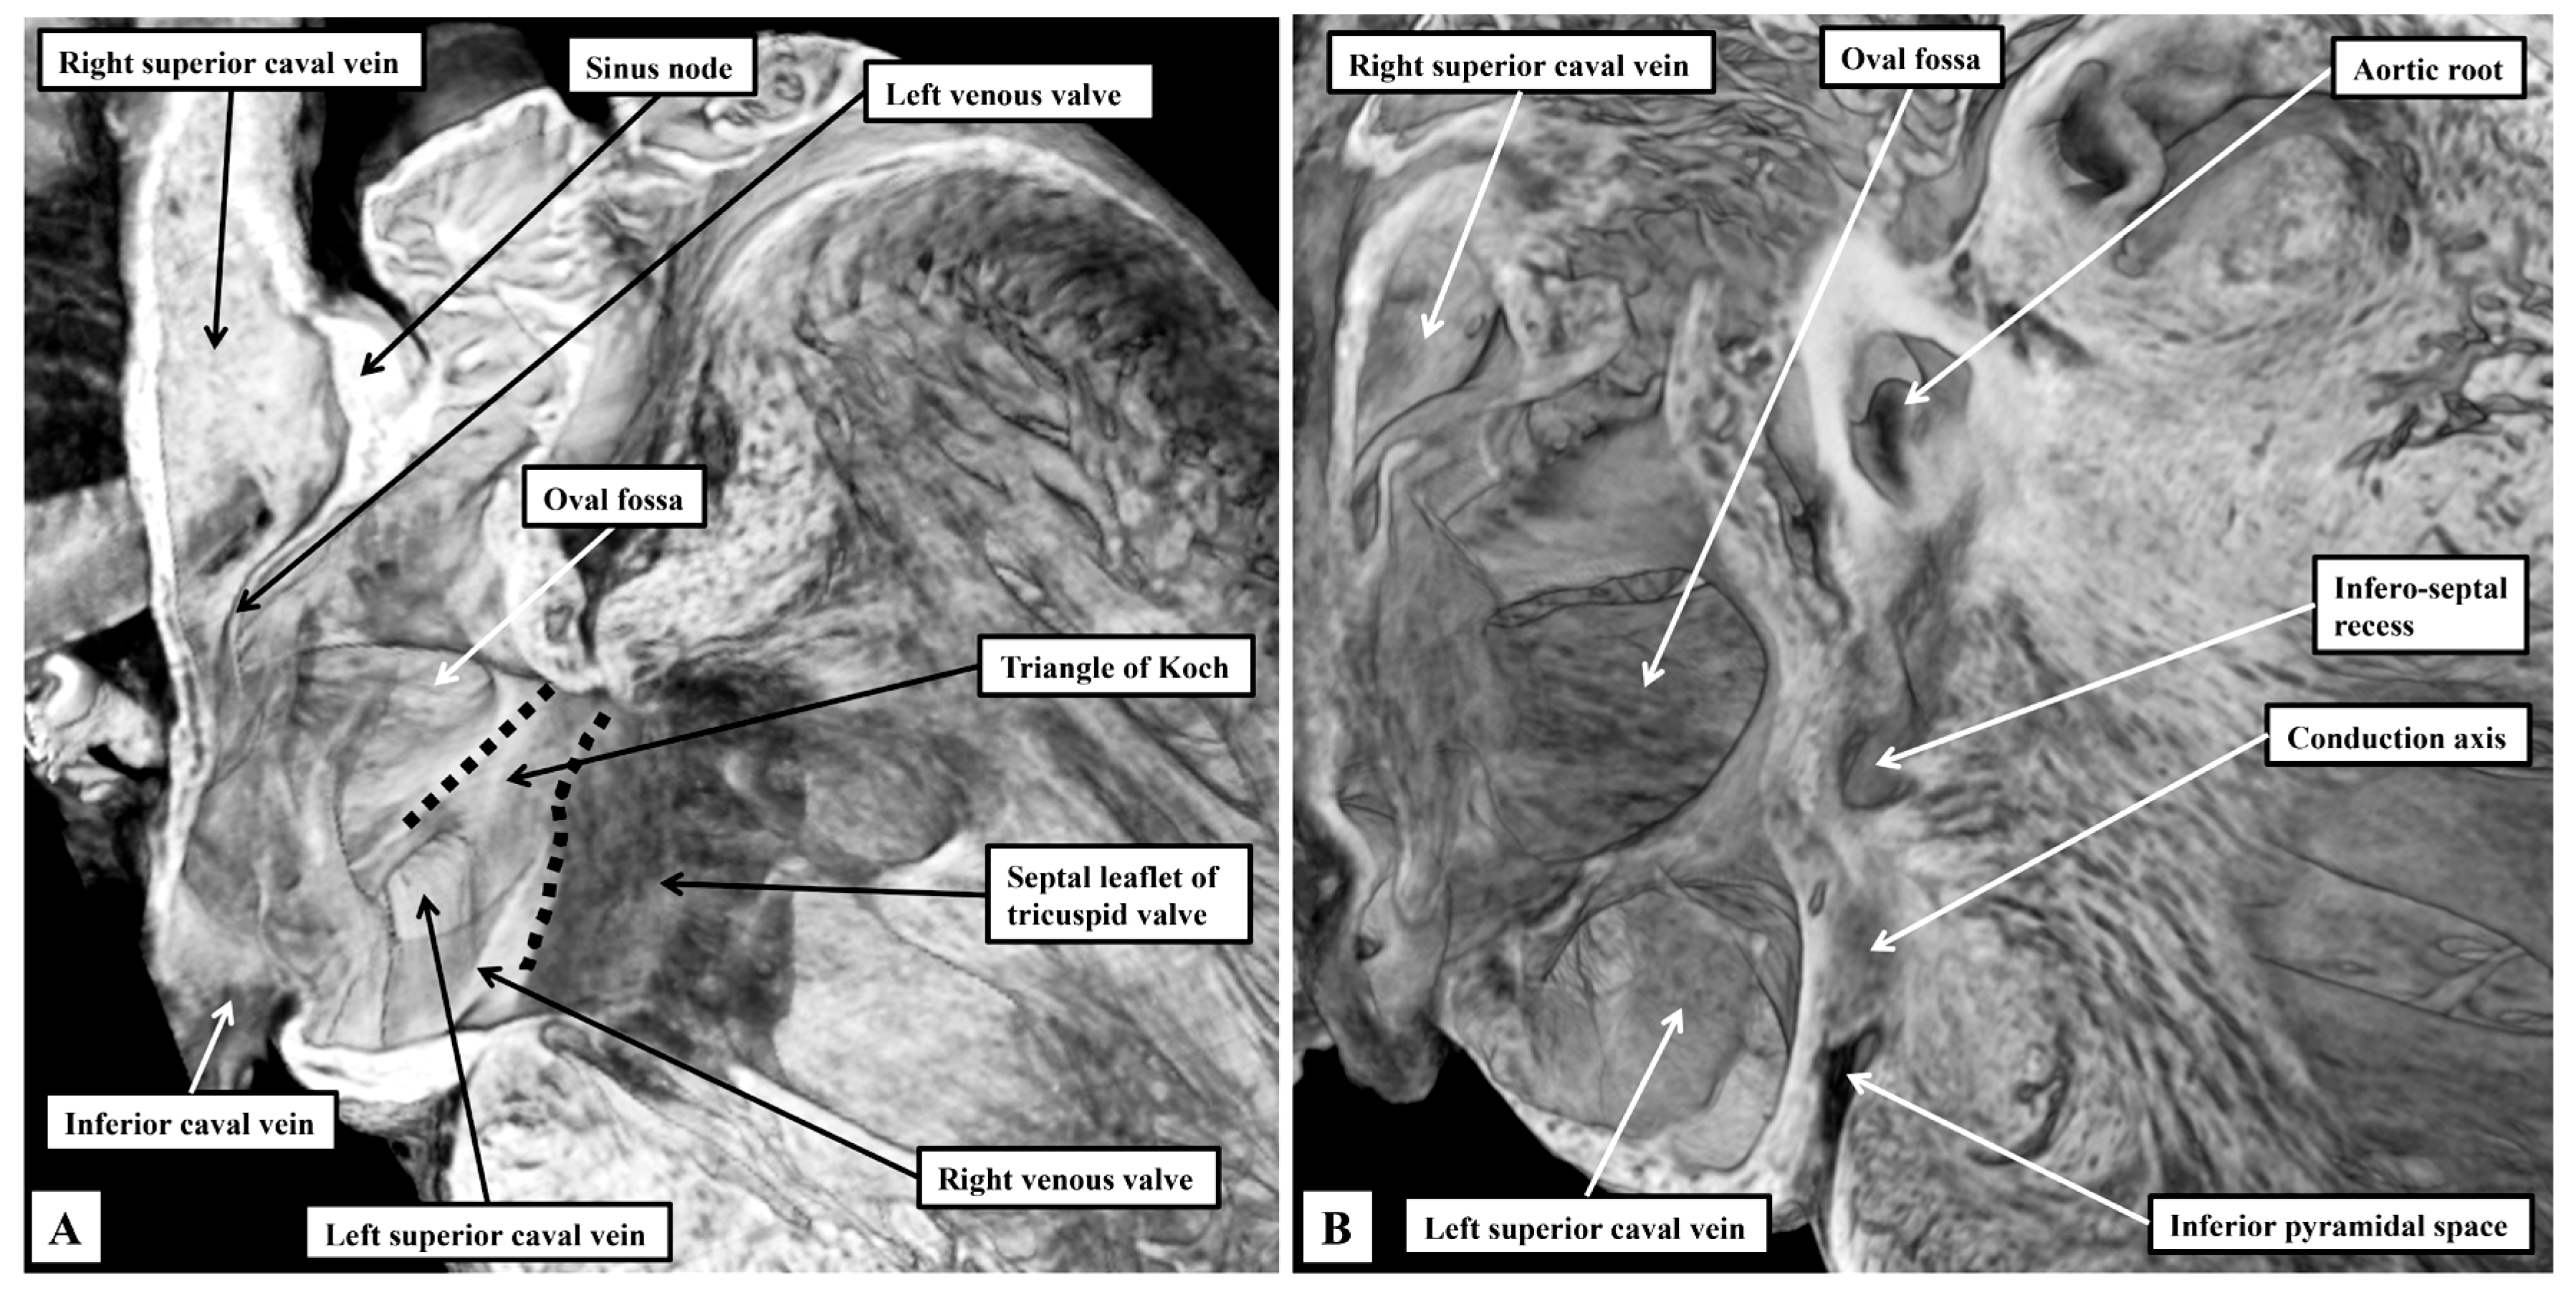

3.2. The Arrangement of the Conduction Tissues